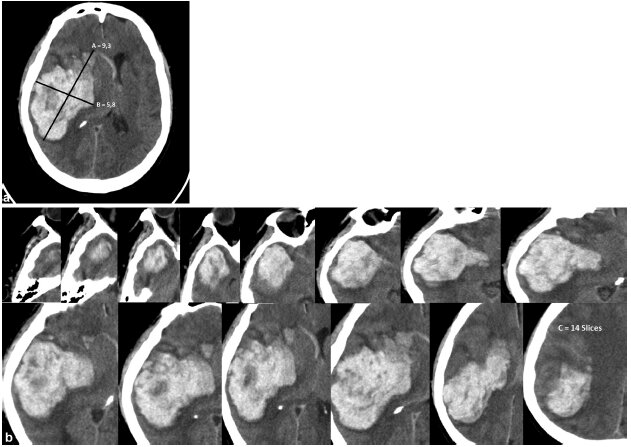

• La TC se utiliza para detectar un tumor cerebral por primera vez.

La TC se utiliza para detectar un tumor cerebral por primera vez.